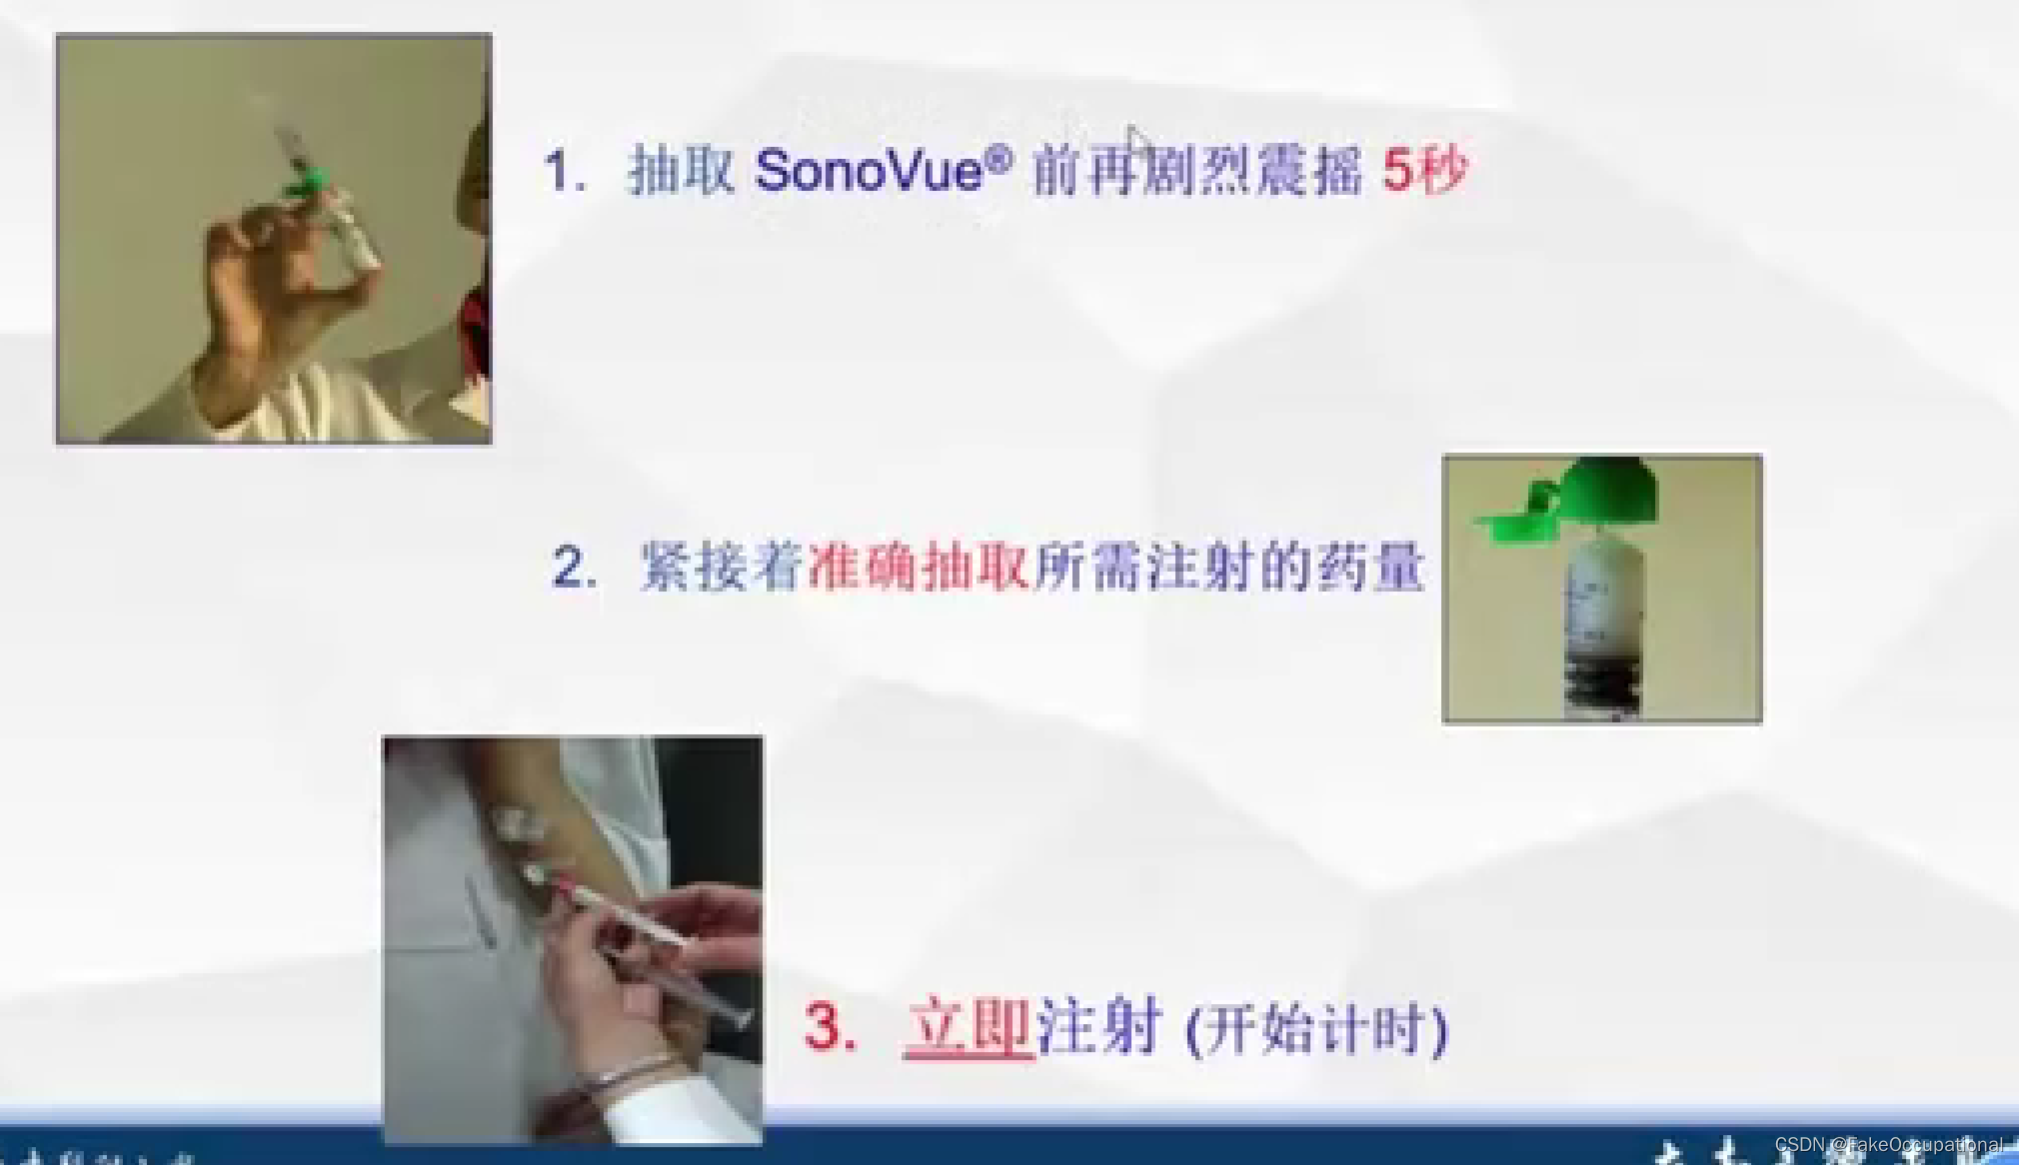

2.超声造影